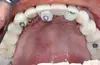

Fig 09 : bridge initial de 11 couronnes céramiques, totalement mobile, sur 8 dents à support osseux détruit. Empreinte primaire physique impossible à réaliser au risque de tout desceller sans possibilité de le replacer, ni d’utiliser le GAM et le GAD.

Étape 7 : dépose à l’arrache-couronne du bridge mobile, GAM clavetté en place.

Fig 13 : dépose du bridge avec 2 racines.

Fig 14 : 6 racines restantes, maintient du guide à appui muqueux après décollement du guide à appui dentaire.

Étape 9 : extractions des racines restantes, GAM en place.

Fig 15 : sites d’extraction avec décollement de la gencive.